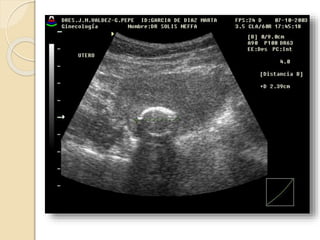

POLIPO ENDOMETRIAL

Se forman por una proliferación

anómala focal o multifocal de la capa

basal del endometrio y del estroma.

Son mas sensibles al estímulo

estrogénico y por esto es frecuente que

coexistan con una hiperplasia

endometrial.

Pueden ser sésiles o pediculados, únicos o múltiples y de

tamaño variable.

Suelen ser hiperecogénicos y en su espesor pueden

apreciarse pequeñas imágenes econegativas quísticas de

diferente tamaño.

Con la ayuda del Doppler color podemos identificar el

pedículo vascular.

La histerosonografía diagnóstica con nitidez la existencia

de pólipos endometriales. Incluidos los de dimensiones

reducidas, su numero, localización, su inserción y las

características del endometrio adyacente.